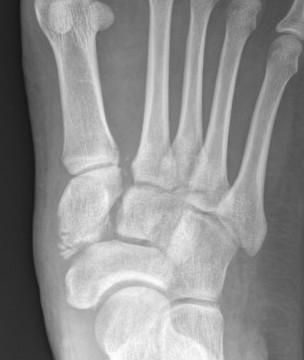

X-ray

Subtle widening of the medial cuneiform - 2nd metarsal distance, and the inter-metatarsal distance

Widening of the medial cuneiform - 2nd metatarsal distance, inter-metatarsal diastasis, fleck sign, possibly increased inter-cuneiform distance

Widening of the medial cuneiform - 2nd metatarsal distance, inter-metatarsal diastasis, fleck sign, increased inter-cuneiform distance